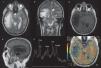

Multiple sclerosis (MS) is a demyelinating disease of the central nervous system, characterized by focal neurological dysfunction with a relapsing and remitting course. Tumor-like presentation of MS (or “tumefactive”/“pseudotumoral” presentation) has been described before with a certain frequency; it consists of a large single plaque (>2cm) with presence of edema and mass effect and it is hard to distinguish from a brain tumor. However, we present a very rare case of a 53-year-old woman with a right temporal mass that turned out to be a MS plaque, who deteriorated within hours (brain herniation with loss of consciousness and unilateral mydriasis) and required an emergency craniotomy. We also present a review of the literature. It appears that only 4 cases of emergency craniotomy/craniectomy required in a patient with a tumor-like MS plaque have been reported before.